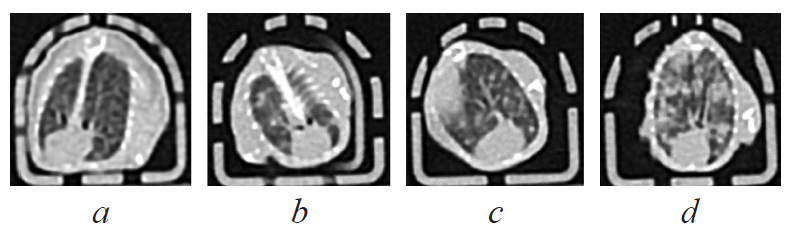

Результаты. У всех мышей из групп 3 и 4 развилась опухоль в месте первичной трансплантации, что было подтверждено визуальной оценкой и результатами гистологического исследования. Рост опухоли в основной группе был достоверно меньше, чем в группе контроля опухоли, что может быть связано с интоксикацией на фоне инфицирования туберкулезом. У всех инфицированных мышей из групп 2 и 4 развился туберкулез легких, подтвержденный данными компьютерной томографии, бактериологическим и гистологическим исследованием образцов легких. Микобактериальная нагрузка в легких оказалась самой высокой у животных с сочетанной патологией туберкулеза и опухоли. Выживаемость мышей определялась в значительной мере ростом опухоли, чем прогрессированием туберкулезной инфекции.